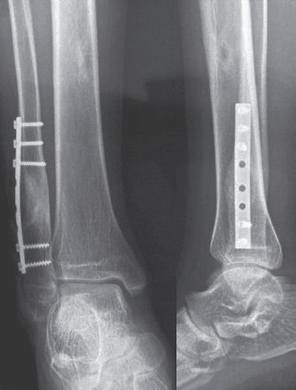

男,15岁,右踝部间断疼痛2年,加重伴右踝部肿胀1周。查体:右外踝上6cm处略肿胀,局部皮温正常,未触及包块,局部压痛明显,右踝关节活动度基本正常。右胫腓骨正侧位平片(图1):右腓骨远端干骺端膨胀性骨破坏,骨密度减低,骨皮质变薄,病灶内有分房,未见骨膜反应及周围软组织影。胫骨中下段髓腔内可见类圆形影,边界清楚,骨皮质无破坏。右踝MRI示:腓骨下段髓腔内显示4.5cm×2cm等T1、短T2异常信号灶,边界清楚,信号不均,其内可见分隔,病灶呈膨胀性生长,骨皮质变薄(图2)。右胫骨中下段髓腔内显示3.7cm×1.7cm椭圆形长T1、T2信号灶,边界清楚,信号均匀,边缘规则,骨皮质连续。结合病史及影像学表现考虑为良性病变,遂在硬膜外麻醉下行右腓骨远端病灶刮除、异体骨植骨、内固定术,右胫骨病灶刮除术。术后病理报告:(1)右腓骨远端髓腔内有5cm×4.5cm×1.3cm肿块。镜下见大片的梭形细胞伴有较多体积较大的多核巨细胞,局部见新生的骨小梁样结构,结合临床,考虑为GCT(图4)。(2)右胫骨远端髓腔内见灰黄色结节肿物,总体积3.5cm×3cm×1cm,镜下显示成熟的脂肪细胞并见增生小血管,结合临床考虑血管脂肪瘤(图5)。术后2周切口愈合良好,无红肿渗出现象,术后3个月患肢行走步态接近正常。术后10个月X线片见腓骨植骨融合,无明显骨破坏,胫骨开窗处可见骨修复(图6)。